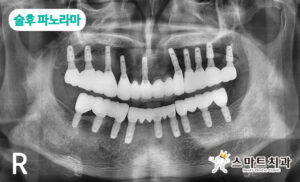

치료하는 기간 동안에는 저작기능 저하로 잠깐 불편했지만 치료가 종결된 후에는 좋아진 저작기능으로 인해 만족도가 매우 높고 삶의 질이 달라졌다고 말씀해 주시며 환자분 가게에 방문하는 손님분들에게 반송치과 추천하는 곳으로 본 원을 적극 추천과 홍보해 주셨는데요, 그 뿐만 아니라 최종 보철물이 들어가는 날 전 직원 모두가 배불리 먹어도 넉넉할 만큼의 회를 직접 준비하셔서 감사했습니다.